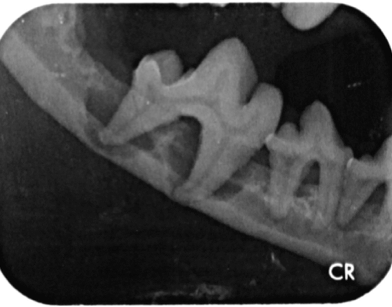

In Narkose sah man auf Leilas Röntgenbildern dann das gesamte Ausmaß ihrer Zahnerkrankung. Bis auf die Canini wiesen alle Zähne hochgradige Wurzelentzündungen mit Osteolysen des Kieferknochens auf. Deshalb konnte man auch schon von außen die Zahnhälse freiliegend sehen. Im Wurzelbereich waren die Veränderungen so schlimm, dass der Unterkiefer kurz vor einer Fraktur stand.

Solche Veränderungen treten oft bei einer hochgradigen Parodontitis auf. Eine Parodontitis ist die Entzündung des gesamten Zahnhalteapparates (also des Kieferknochens, des Zements, der Paradontalfasern und des Zahnfleischs) und wird durch die Bakterien, welche im Plaque enthalten sind, hervorgerufen. Diese zerstören die Anheftung der Gingiva am Zahn, und die Bakterien können bis zur Wurzel vordringen. Hier rufen sie Entzündungsreaktionen des Kieferknochens und der Gingiva hervor, wodurch beide sich zurückziehen und tiefe Paradontaltaschen entstehen lassen. Doch Leila hatte, wie auf den Bildern schön zu sehen ist, kaum Zahnstein oder Plaque.

Es ist sehr wichtig zu verstehen, dass eine Zahnreinigung ohne Aufnahme eines kompletten Zahnstatus inklusive Zahnröntgen nichts weiter ist als eine kosmetische Behandlung, da krankhafte Prozesse übersehen werden (abb. 7-10).